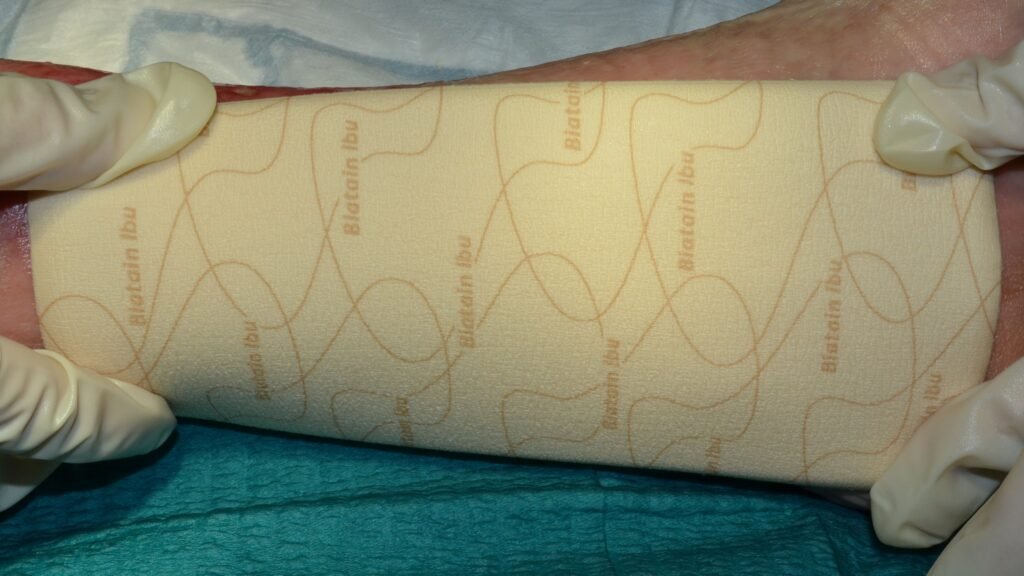

Der weiche und gut applizierbare Biatain Alginate ![]() (3) Alginatverband ist durch den Zusatz von Calciumalginat und Carboxymethylcellulose (CMC) ein sehr stark absorbierendes Produkt. Hohe Reißfestigkeit und hohe Gelintegrität zeichnen Biatain Alginate zusätzlich aus.

(3) Alginatverband ist durch den Zusatz von Calciumalginat und Carboxymethylcellulose (CMC) ein sehr stark absorbierendes Produkt. Hohe Reißfestigkeit und hohe Gelintegrität zeichnen Biatain Alginate zusätzlich aus.